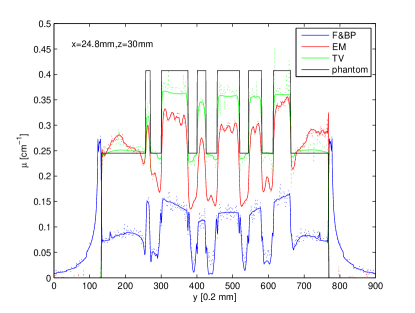

In Figs. 3, and 4, we show the image profiles on three different lines through the reconstructed image within the center plane (i.e., mm) of the image. The reconstruction properties discussed above can be observed in these profile results. Clearly, the FBP reconstruction appears most noisy, which is expected because the ramp filtering tends to amplify noise. There is a considerable DC shift for FBP reconstruction, as well as for the EM reconstruction. From the profile across spheres of varying diameters in Fig. 3, it can be observed that that in-plane resolution is maintained in DBT, which is the reason for the clinical usefulness of DBT. The profile in Fig. 4 is on a line through a uniform section of the phantom. Uniformity appears to be best reproduced by the TV reconstruction. In the TV reconstruction, a shift between noiseless and noisy data can be observed.